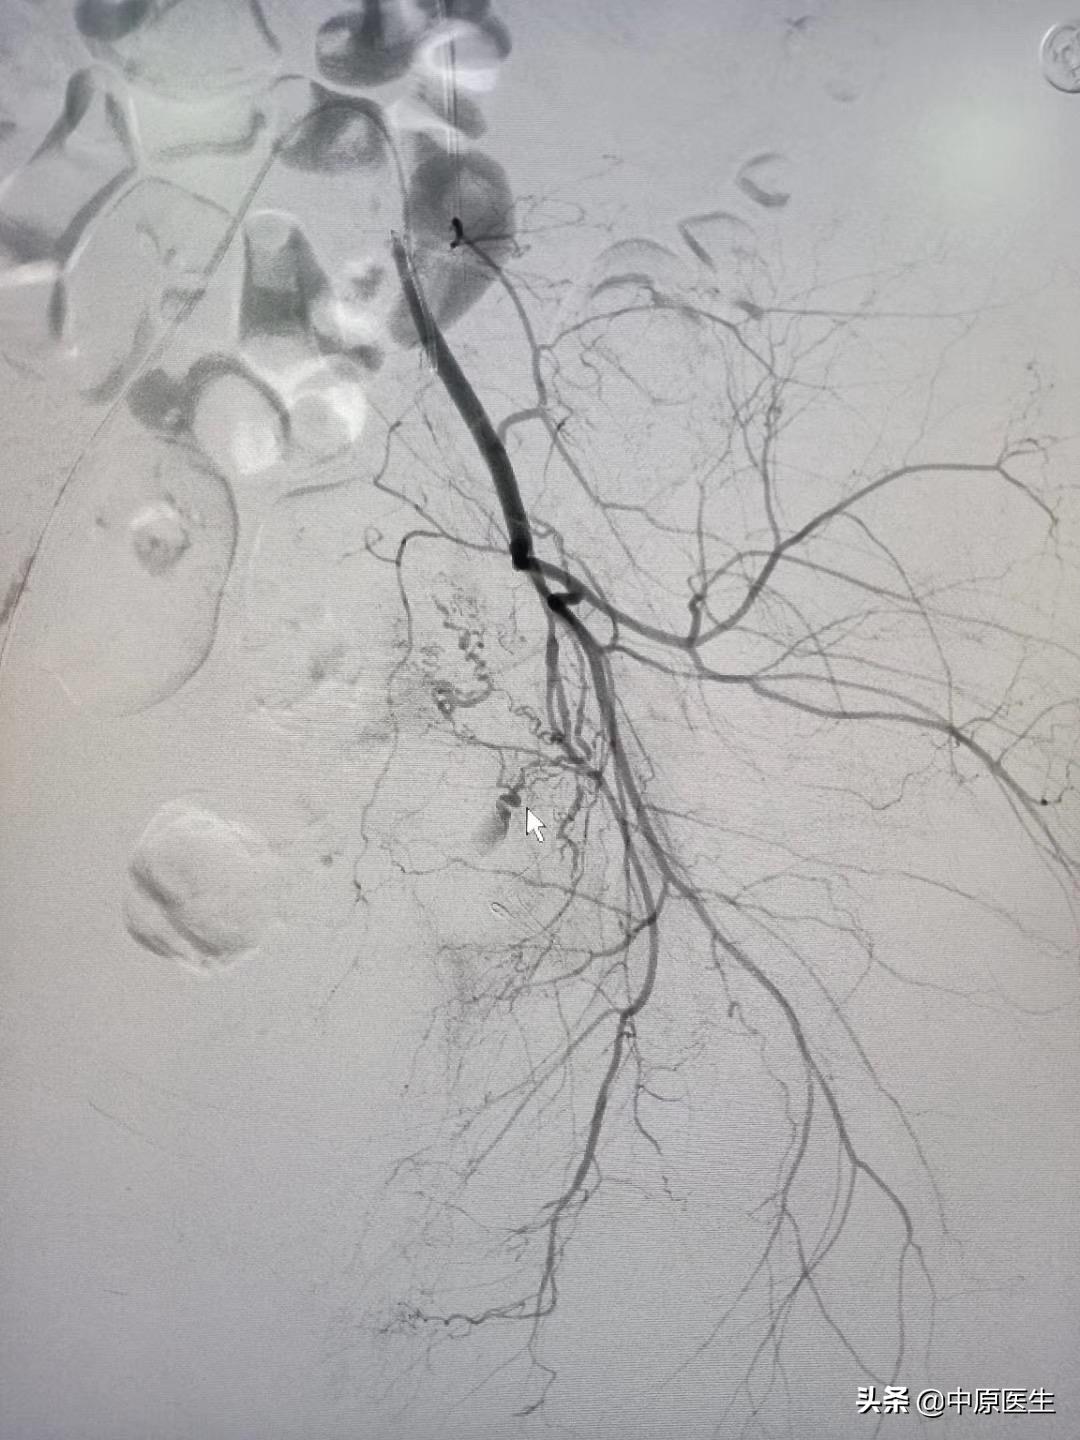

我处理好门诊事宜,十点赶往导管室,按标准预防做好术前防护、术前准备工作。在导管室的护士、技师等积极配合下,手术顺利开展,造影显示左侧子宫动脉近宫颈处有一破口、形成假性动脉瘤,假性动脉瘤破溃,造影剂快速流入宫腔内(相当于找到了河流的决口处);紧急用生物胶栓塞该破口及其远、近端血管(相当于堵住了决口及其上下游,上游流不进来、下游的倒灌不了),复查造影未见造影剂外渗、动脉瘤、静脉早显等异常血管影(成功止血)。然后选择双侧髂内动脉各分支造影未见明显异常血管,再予右侧子宫动脉栓塞。半小时顺利完成手术,病人生命体征平稳。安全送回病房,继续药物治疗。